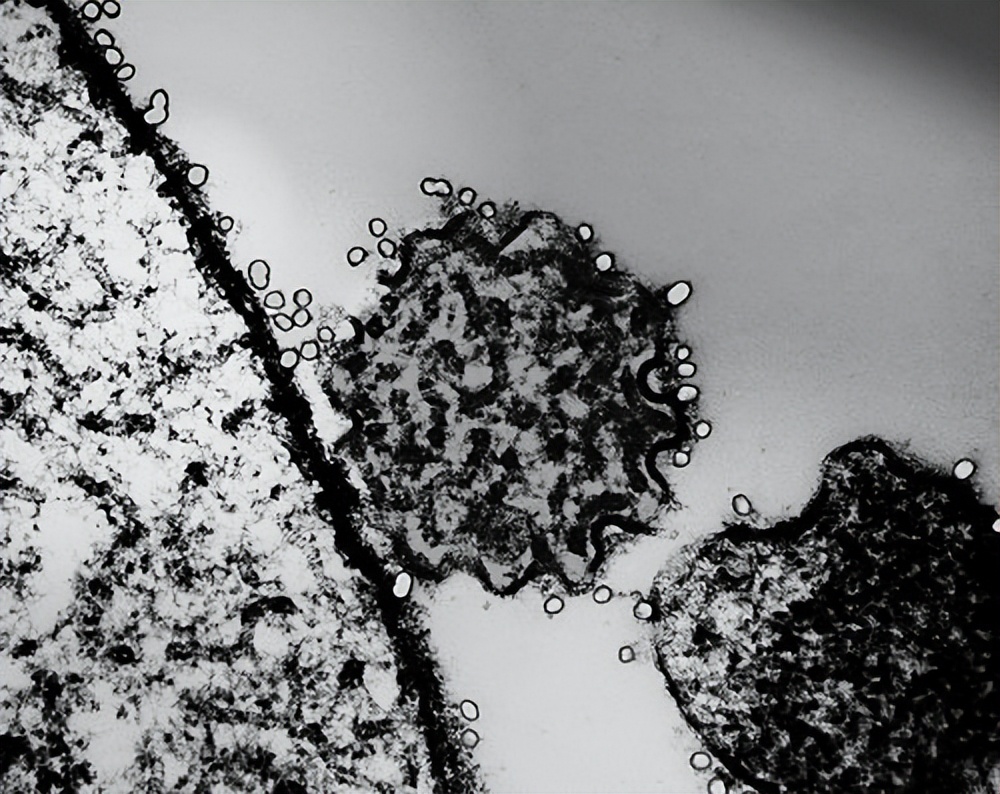

尼帕病毒是一种人兽共患病毒,属于RNA病毒,副粘病毒科。病毒颗粒呈多形性,直径150-300纳米,最外层为脂蛋白包膜。